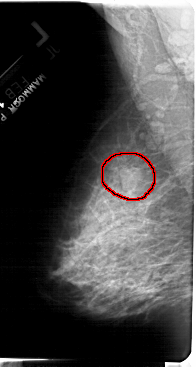

A_1397_1.RIGHT_CC

RIGHT_CC LINES 5371 PIXELS_PER_LINE 2761 BITS_PER_PIXEL 12 RESOLUTION 43.5 OVERLAY

FILE: A_1397_1.RIGHT_CC.OVERLAY

TOTAL_ABNORMALITIES 1

ABNORMALITY 1

LESION_TYPE MASS SHAPE LOBULATED MARGINS OBSCURED

ASSESSMENT 4

SUBTLETY 3

PATHOLOGY BENIGN

TOTAL_OUTLINES 1

BOUNDARY